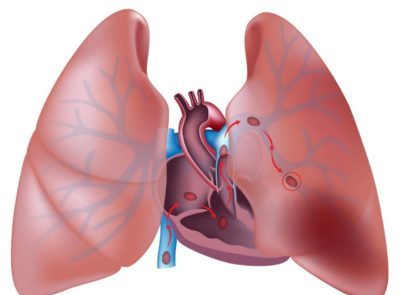

Плеврит представляет собой воспаление плевры – соединительнотканной пленки, покрывающей легочную ткань и внутреннюю поверхность стенок грудной полости. Она имеет два листка – висцеральный и париетальный. Между ними есть щель, именуемая плевральной полостью. В норме в ней находится немного жидкости, которая выполняет функцию смазки, облегчая процессы вдоха и выхода.

Различают две формы недуга: экссудативная и сухая. При первом виде происходит усиленная выработка секрета, ухудшается его впитывание и жидкость накапливается в полости плевры. При сухой форме на поверхности висцерального и париетального листков скопляется фибрин. Кроме того, иногда встречается гнойной плеврит. При онкологических недугах зачастую возникает экссудативная форма.

Главная опасность недуга – возникновение сердечно-легочной недостаточности. Ее развитие связано со смещением органов средостения, которые давят на сосуды, пытающие сердце и повышают давление в грудной полости.